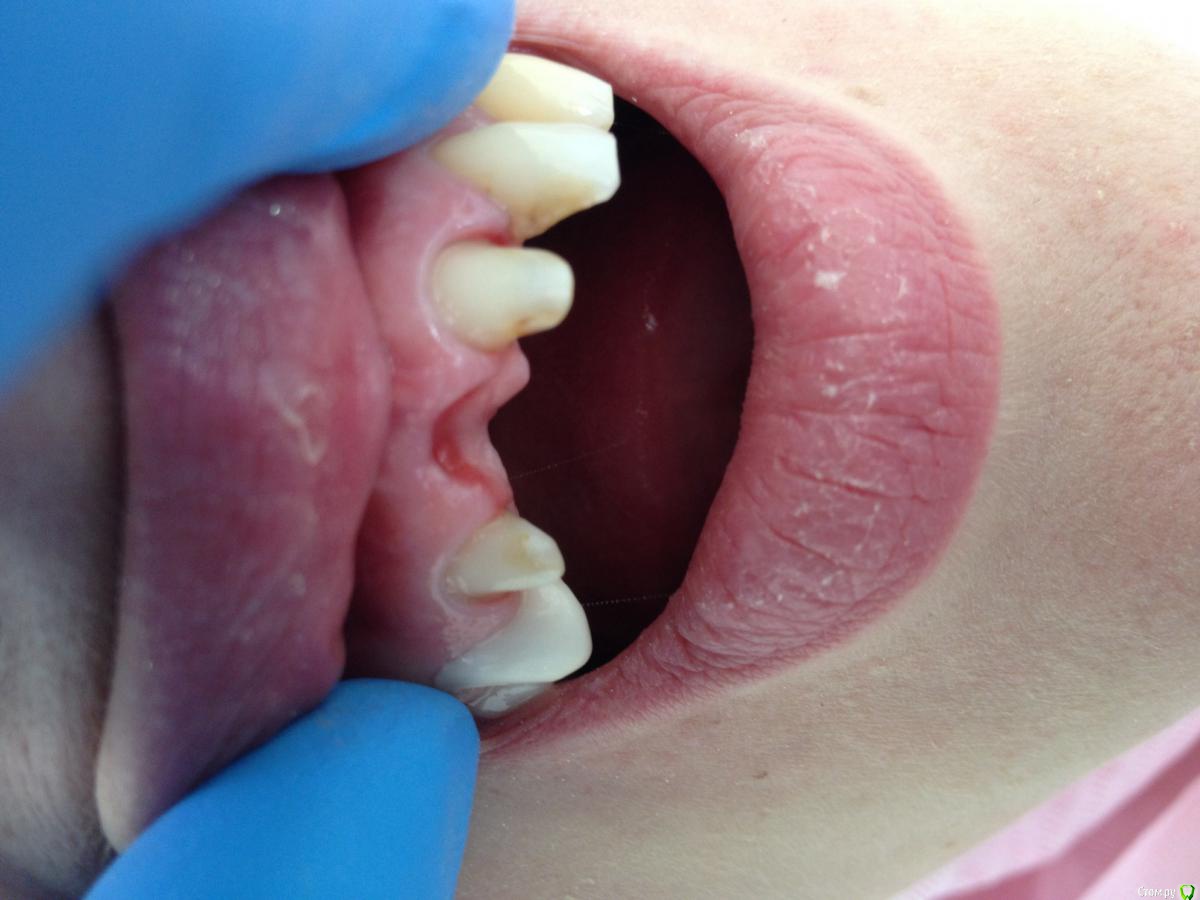

DoctorT Опубликовано 2 апреля, 2015 Поделиться Опубликовано 2 апреля, 2015 (изменено) Решил побаловаться и сотворить овоид))) Изменено 2 апреля, 2015 пользователем DoctorT 1 Ссылка на комментарий

molchanoff Опубликовано 2 апреля, 2015 Поделиться Опубликовано 2 апреля, 2015 Решил побаловаться и сотворить овоид)))себя побаловать?в позиции 11 не овойд под мост, а имплант нужен.а то вы соединили жесткой конструкцией кости в.ч. и радуетесь. Ссылка на комментарий

DoctorT Опубликовано 2 апреля, 2015 Поделиться Опубликовано 2 апреля, 2015 (изменено) Т.е. мост есть противопоказан? Вы считаете, что зубы в кости анкилозированы, не имеют связочного аппарата и абсолютно не подвижны и имплантация это панацея? Я согласен, что лучшим вариантом могло быть установка имплантов в позиции отсутствующих зубов. Но радикально отвергать мостовидные протезы я не стану. Изменено 2 апреля, 2015 пользователем DoctorT Ссылка на комментарий

molchanoff Опубликовано 3 апреля, 2015 Поделиться Опубликовано 3 апреля, 2015 21 не соединяйте с остальными опорами Ссылка на комментарий